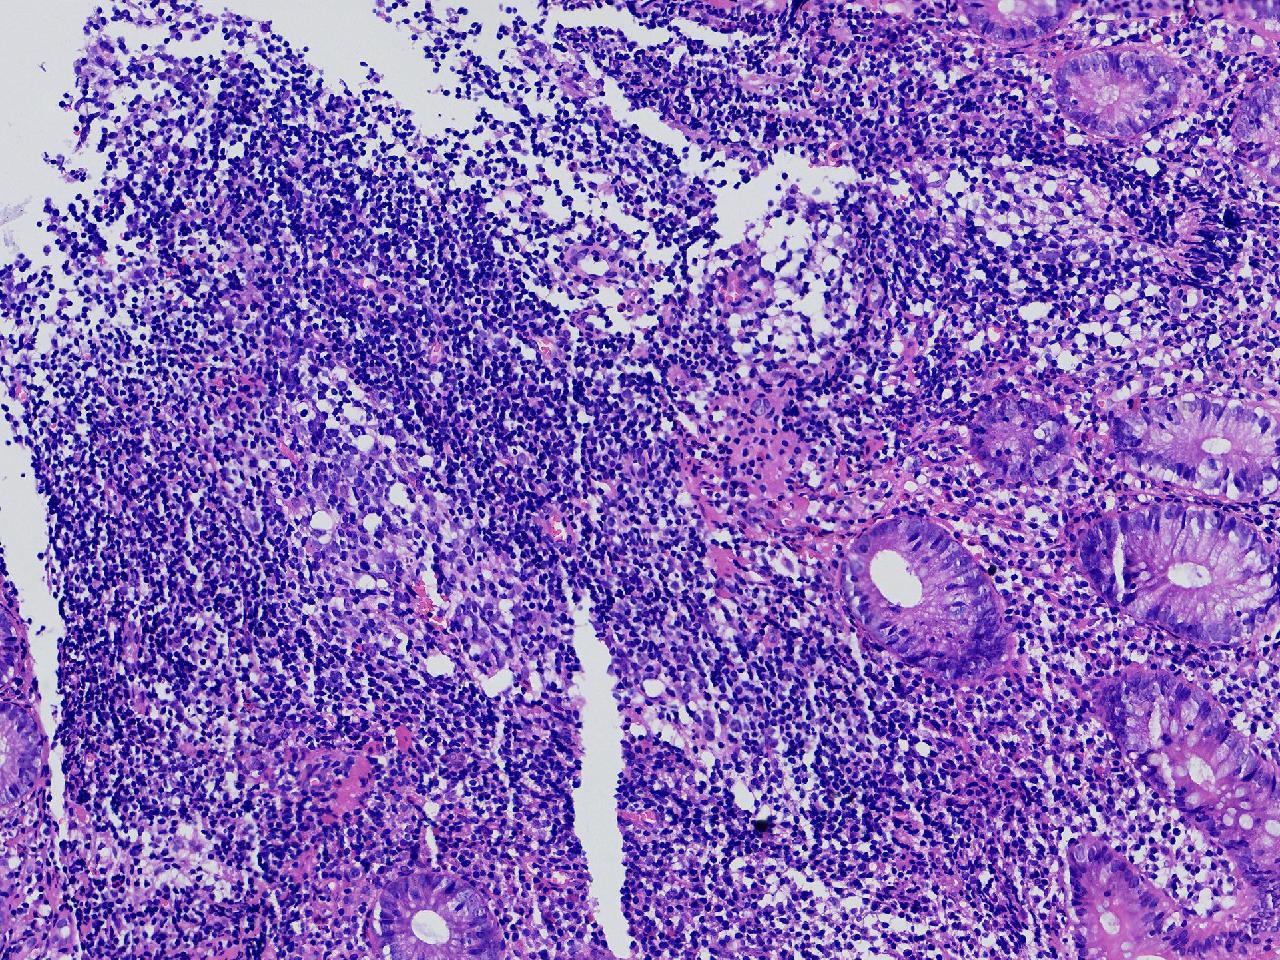

男,62岁,回盲部附近见多发片状溃疡,底覆薄白苔,周围粘膜充血水肿,活检2块,质软,弹性可。

回盲部活检

灰白色不整形软组织2块,直径均0.2厘米。

考虑:溃疡性结肠炎?

炎症性肠病要考虑,具体的类型不太好确定,需要结合临床。

上级医院会诊,不除外炎症性肠病,结合临床。